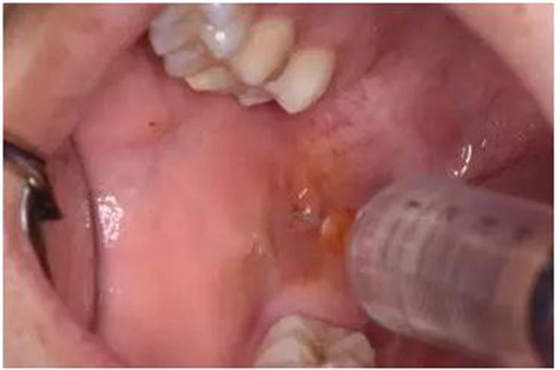

圖4.局部注射區(qū)粘膜碘伏消毒

圖5.行下牙槽神經(jīng)阻滯麻醉